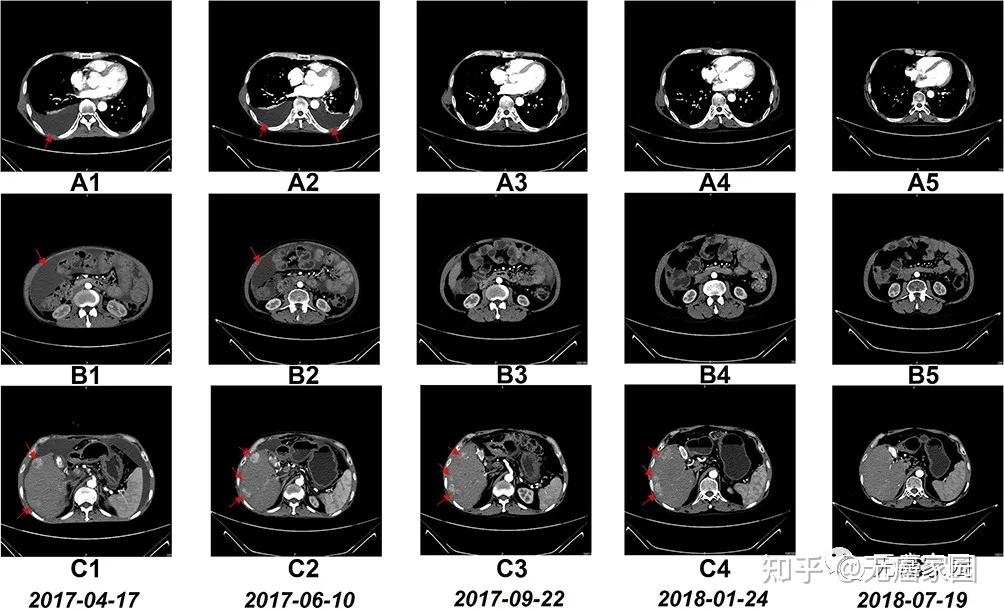

共156名受试者参与Ⅱ期临床试验,他们均为CLDN18.2阳性的晚期胃癌或胃食管结合部癌患者,且对至少两种先前治疗耐药。受试者被随机分配到使用舒瑞基奥仑赛注射液治疗组(104人)或医生选择的标准疗法治疗组(52人),标准疗法包括使用紫杉醇、纳武利尤单抗或阿帕替尼等药物。试验结果显示,与标准疗法相比,舒瑞基奥仑赛注射液治疗显著延长了患者无进展生存期,且安全性较高。